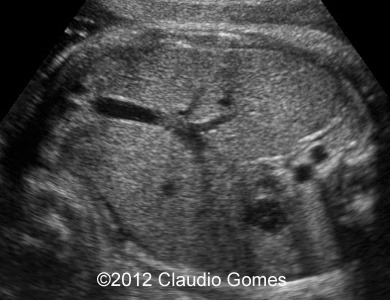

At 21 weeks 5 days, we found an isolated persistent right umbilical vein.

Image 1: At 21 weeks, persistent right umbilical vein ( arrow) next to gallbladder (*)

f1